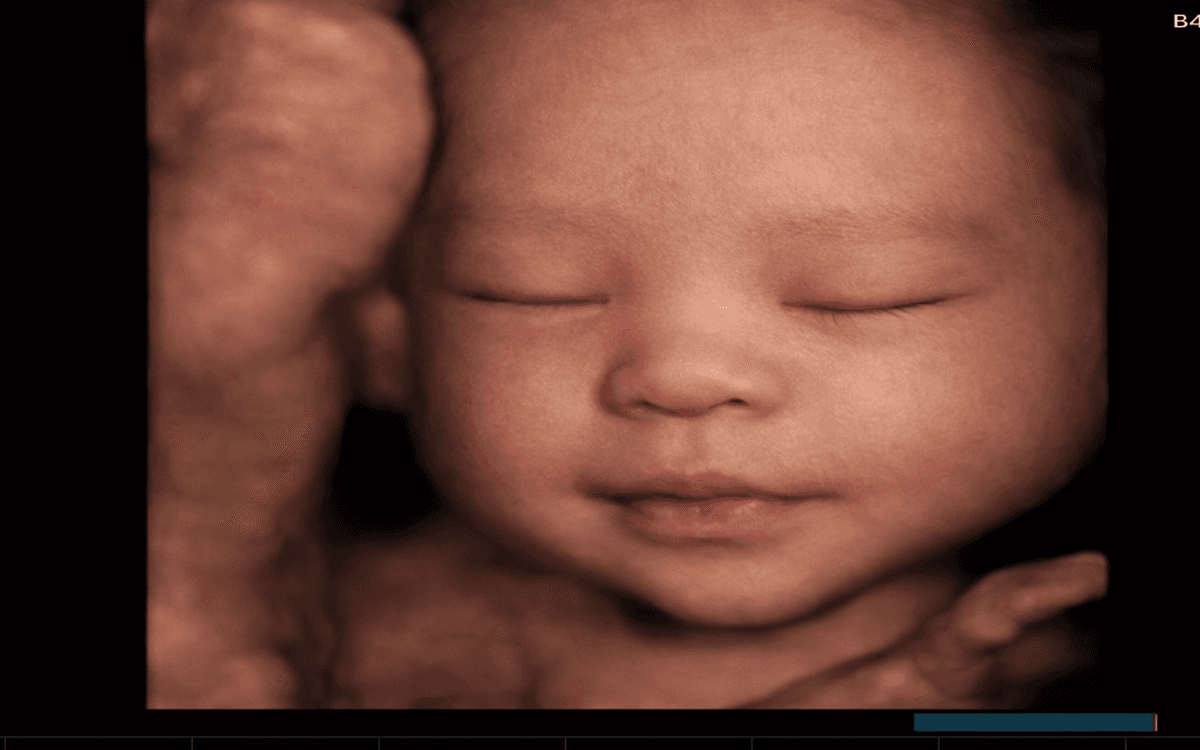

Vuốt để xem sự khác biệt giữa ảnh siêu âm gốc và hình ảnh AI làm nét

Công nghệ AI của LovelyBaby phân tích cấu trúc xương, làm rõ nét từng đường nét chân thực nhất trên khuôn mặt bé để tạo nên bức ảnh kỷ niệm tuyệt đẹp theo bạn suốt đời.

Hệ thống tự động phân tích và làm rõ nét khuôn mặt chỉ trong 30 giây.